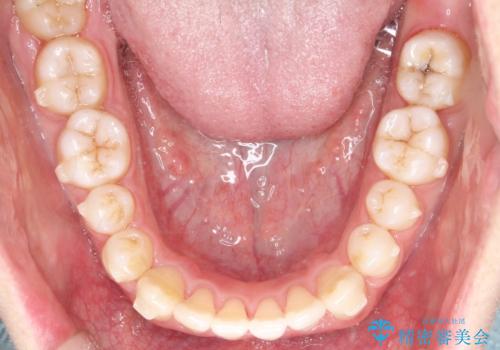

- 前歯のすきっ歯が気になると来院された患者様です。

前歯の隙間をマウスピース矯正(インビザライン)を使用して、閉じていきました。